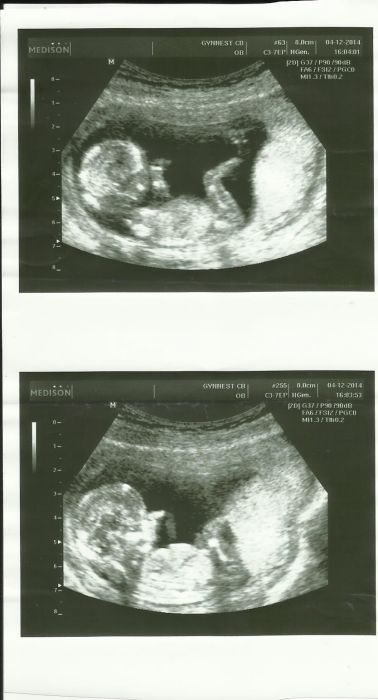

Já na screenu byla a jsem poslaná i na tripl test. Zasílám slíbený ultrazvuk.

Ahojky je holky u nás vše při starém SCR az 23 tak odskrtavam ne do vánoc ale do gyndy :D Ivo také mám už druhy den zvláštní pocit v zubu ne primo bolet ale takový to "cukani" a to mi ho červen az září léčila tak se úplně delším aby me to nechytlo opět ;/ FOTA utz nádherná jak už je vidět ze je to opravdu miminko se vším všudy ;-* Já myslím ze můj dr taky něco říkal ze je jen jeden odběr tak předpokládám ze to bude na úkor tripplu ze ho nedělá u malého mi ho zapomněli udělat což jsem rada když jsem pak koukala jak je chybovost. My frcime s prckem k dr na 2 letou kuli problémů s kulkama tak snad to bude už OK.